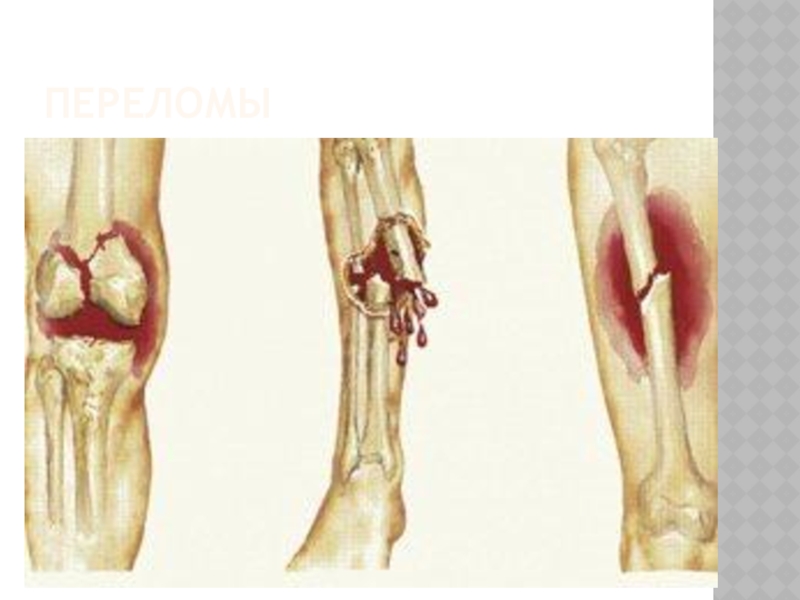

Слайд 3Перелом — это нарушение целостности кости в результате механического воздействия. Переломы

бывают открытыми и закрытыми.

Перелом — это нарушение целостности кости в результате механического воздействия. Переломы бывают открытыми и закрытыми.Вывих — это

Слайд 14ПРИЗНАКИ ОТКРЫТОГО ПЕРЕЛОМА

деформация и отечность конечности в месте повреждения , обязательное наличие раны, из

просвета раны могут выступать костные отломки.

ПРИЗНАКИ ОТКРЫТОГО ПЕРЕЛОМА деформация и отечность конечности в месте повреждения , обязательное наличие раны, из просвета раны могут выступать костные отломки.

Слайд 15ПЕРЕЛОМЫ

ПЕРЕЛОМЫ